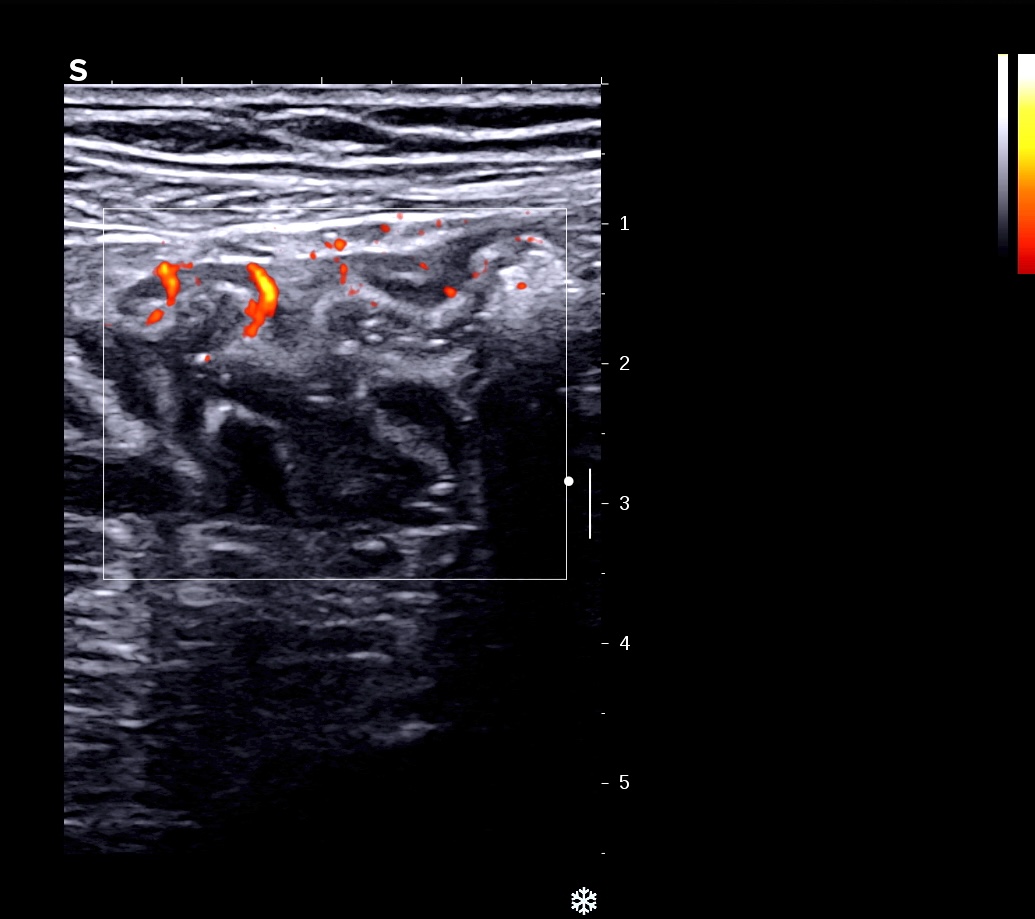

*Paroi antérieure et postérieure accolées, hypoéchogènes et doppler *

Surface irrégulière ulcérée